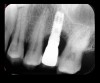

Following a similar paradigm of treating peri-implantitis the same way that periodontitis is regularly successfully treated, based on the mechanical removal of biofilms adhered to implant/abutment surfaces, different protocols of nonsurgical implant debridement using different mechanical, physical, and chemical mechanisms have been evaluated (Figure 12 through Figure 15). In general, the use of different protocols combining treatments aimed to decontaminate the implant surface (eg, mechanical, lasers) and control the infection process (eg, antiseptics, antibiotics) have shown clinical and significant improvements in the commonly used surrogate outcomes (mean reductions in PPD of around 1.2 mm and mean reductions in the scores of BOP of about 50%) but have not resulted in disease resolution18 or a high degree of predictablility.19 There is currently no specific nonsurgical therapy that has shown efficacy in the resolution of peri-implantitis, and the clinical improvements reported in the clinical studies were not sufficient for the arrest of the disease, leaving the standard of care in the treatment of peri-implantitis as surgical in most cases.20

Fig 12. Treatment of peri-implantitis: peri-implant mucosal inflammation associated with plaque and calculus accumulation.

Figure 12

Fig 13. Radiograph depicting crestal bone loss around mandibular implants.

Figure 13

Fig 14. After removing the prosthesis, presence of peri-implant plaque and calculus.

Figure 14

Fig 15. Access flaps to allow mechanical debridement of implant surfaces.

Figure 15